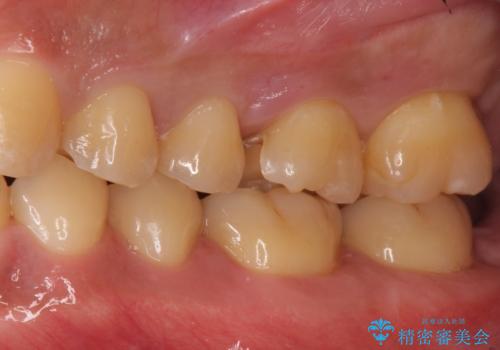

- 奥歯が虫歯になっていたため、セラミックインレーで修復しています。

- 7万円(左上7 emaxプレスインレー 7万円)費用は治療当時の料金となります

セラミック治療の注意事項(リスク・副作用など)

- 天然歯を削ります

- 硬い素材は天然歯を傷つけてしまう場合があります

- かみ合わせや歯ぎしりが強すぎる方はセラミックが割れてしまう可能性があります

- 自費診療(保険適用外治療)となります